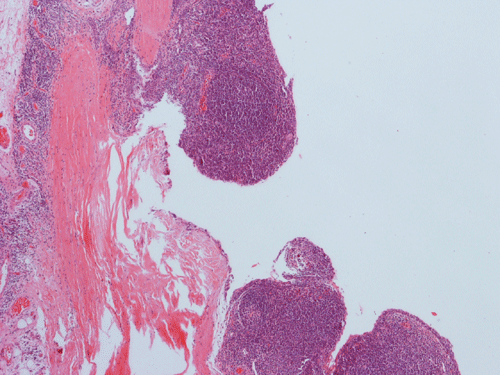

Histopathology: The lesion is encapulated cystic structure with the wall lined by nodules of lymphoid tissue (Panel A  and B) that are devoid of any evidence of hematopoiecic malignancy. Within this lymphoid tissue are small pink islands (Arrow in Panel C) and on higher magnification (Panel D) these islands are squamous cell nests. These islands are Hassell corpuscles and the lymphoid tissue is in fact thymic tissue. The cyst appears to have sustained repeated hemorrages. Both recent hemorrhage (Panel E) and cholesterol clefts consistent with resolved hemorrhage (Panel F) are present.

Cervical thymic cysts can vary in size up to few centimeters, may be unilocular or multilocular. The lateral location is a good clue to support the diagnosis. The cyst contents vary from clear serous fluid to hemorrhagic or purulent fluid. They may contain semi-solid, gelatinous, necrotic debris, blood or cholesterol crystals (like this case). Thymic parenchyma, lymphoid tissue and Hassall’s corpuscles found within the cyst wall are considered pathognomic findings. The cyst wall may be devoid of epithelial lining or may have cuboidal, stratified or ciliated epithelium. Identification of the Hassall’s corpuscles is the key to correct diagnosis and sometimes they may not be abundant. Secondary changes due to hemorrhage are also common findings. Sometimes, pressure necrosis may lead to granulation tissue. No ectopic thyroid tissue should be present. The diagnosis is usually straight forward.